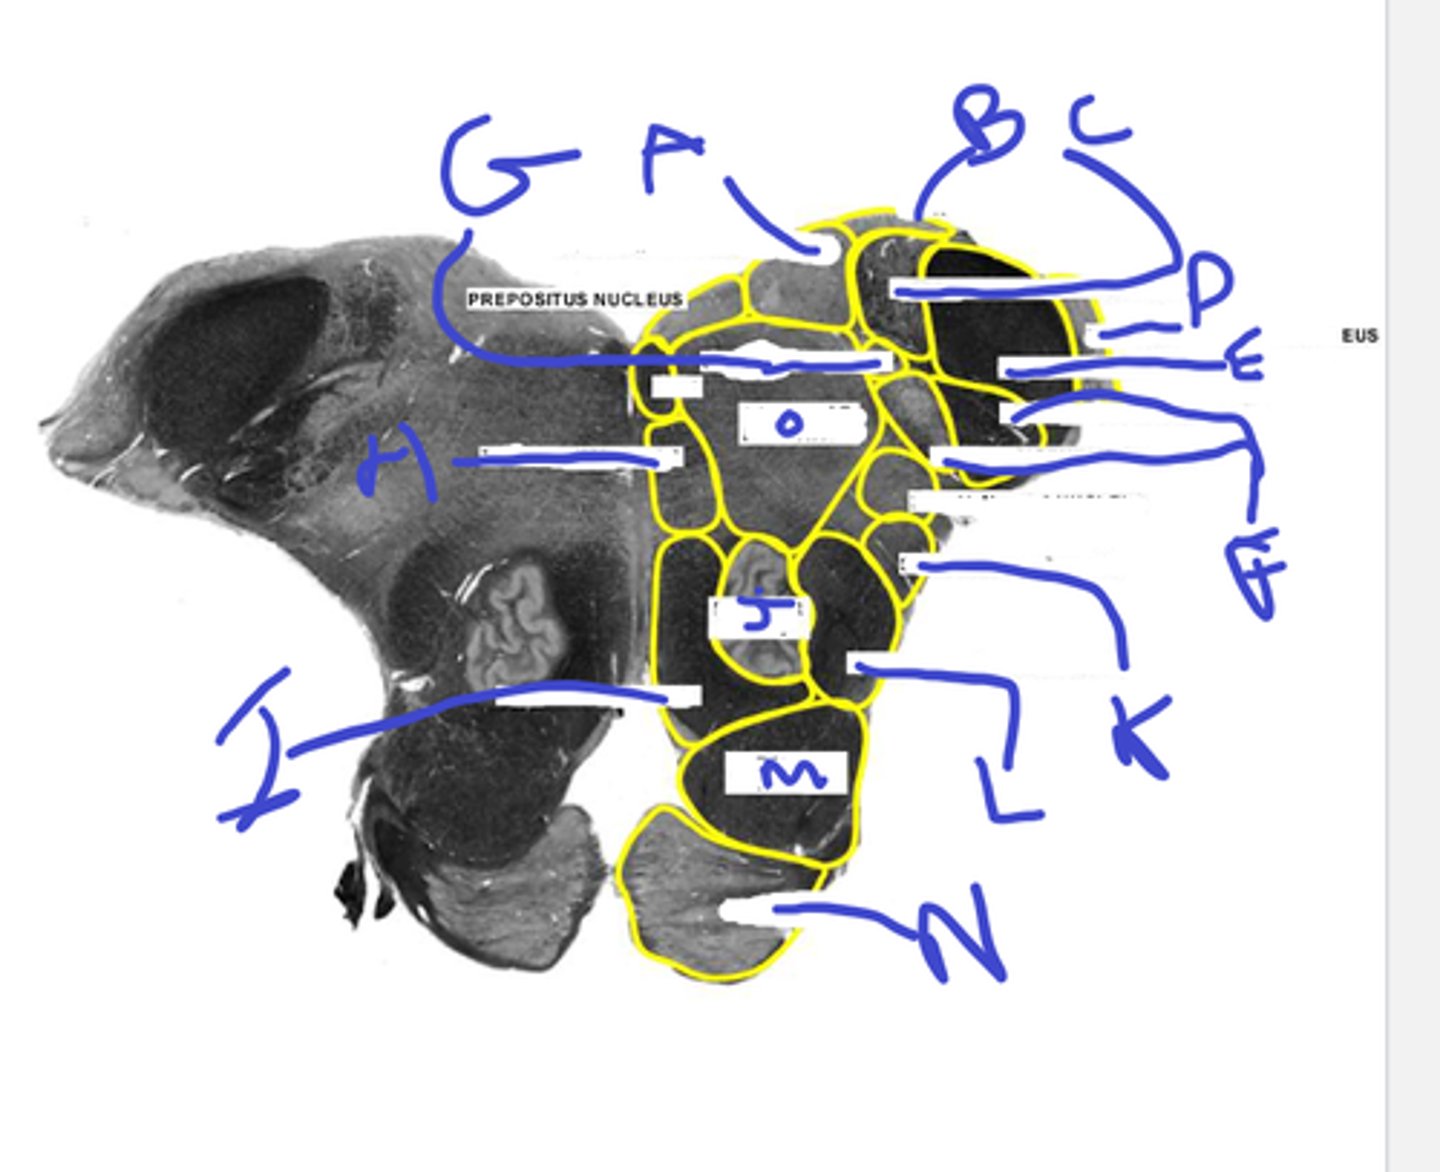

a-med vestibular nuc

b-dorsal cochlear nuc

c-inf vestibular nuc

d-ventral cochlear nuc

e-inf cerebellar peduncle

abcde

f-spinotrigeminal tract/nuc

g-solitary nuc

h- mlf is one circle dorsal

i-medial lemniscus

j-inf olive

fghij

k- spinothalamic

l-central tegmental tract

m-pyr tract

n-pontine nuc

o-reticular formation

klmno